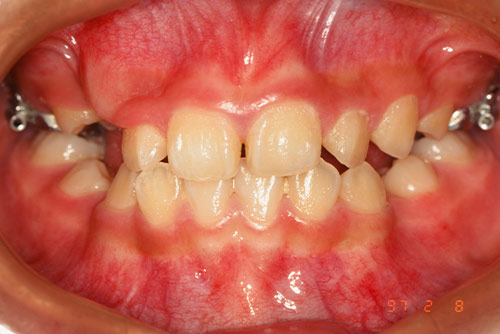

小さな顎に大きな歯が生えると、どうしても歯並びが悪くなります。通常の矯正治療は、ガタガタになった歯を整えるものですが、根本的な治療にはなりません。時間が経つと、歯並びが後戻りすることからも分かります。

歯並びも同じで、「顎のスペースが狭い」と歯が重なりながら生えるしかなく(「叢生」)、結果としてデコボコの歯並びになります。

一方で「子どもの矯正」は、成長を適切な方向に誘導することで無理なく治療を進めることができ、理想の顎の骨格や歯並びにすることが可能です。子どもの矯正は、子どもの「成長力」を利用して、理想的な顎、歯並び、顔貌を形成していけることが最大のメリットです。